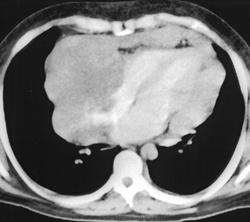

Миксома предсердия

Случай 1: миксома правого предсердия

Случай 2: миома левого предсердия

Случай 3: миксома левого предсердия

Случай 4: миома левого предсердия

Случай 5: миома левого предсердия